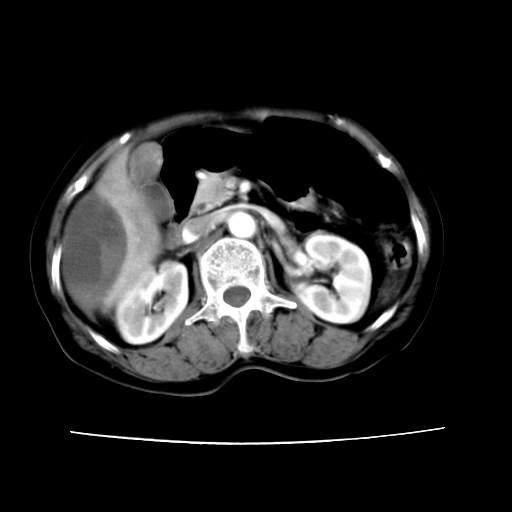

2008-11-10ct平扫(其间去中山医院诊治未行特殊治疗)

2008-11-10ct平扫见并肝内、血膜下血肿基本吸收,肝内低密度灶缩小。此时再做增强ct应有显着意义。对患者/医者都好!

患者自6月至11月,如果是肝癌,没有经过特殊治疗,想必应该会有所进展吧,而不是ct所见,反而似有病灶减小的趋势。建议增强。

病变破裂出血应首先考虑,病变性质即可能是恶性也可能是良性,楼主说患者到上级医院检查未见癌细胞,以良性可能性大,首先考虑腺瘤破裂出血可能。

追问病史,患者有过度用力病史,当时立即感腹痛;所以还考虑肝破裂可能性大。